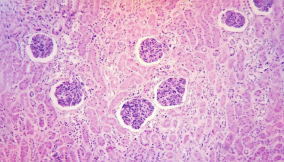

病理学和医学影像学研究平台